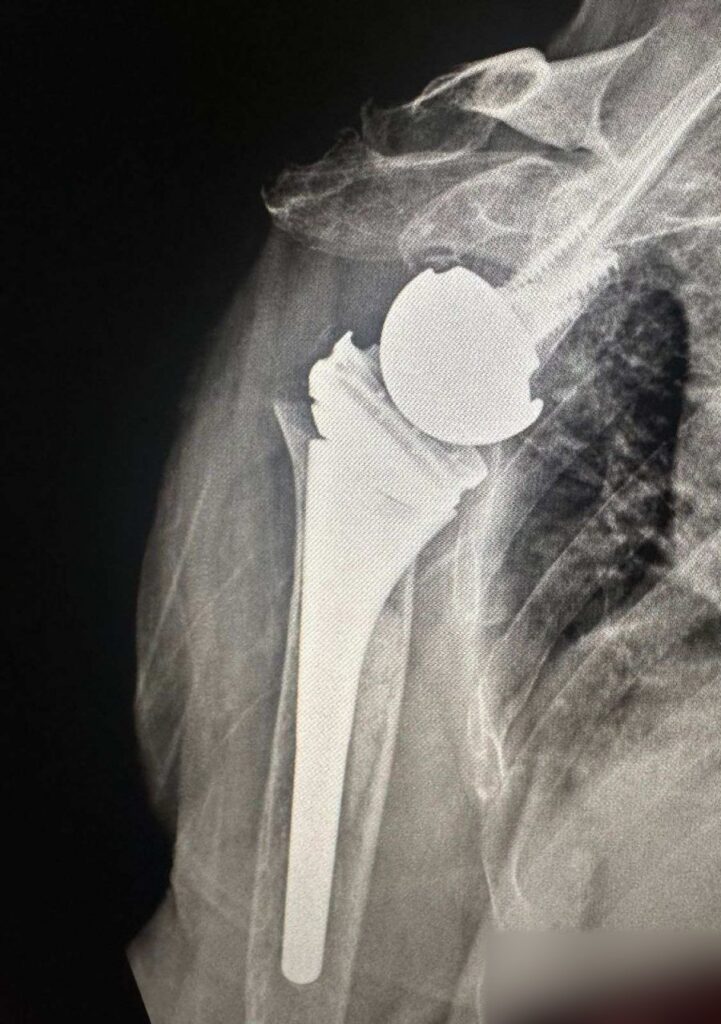

Për herë të parë në Klinikën e Ortopedisë të Qendrës Klinike dhe Universitare të Kosovës janë kryer dy operacione për vendosjen e protezave të supit.

SHSKUK-ja ka njoftuar se ekipi mjekësor në përbërje të dy ortopedëve, si dhe ekipit nga Klinika e Anesteziologjisë dhe stafit infermieror, me sukses të plotë kanë kryer këto dy operacione ortopedike.